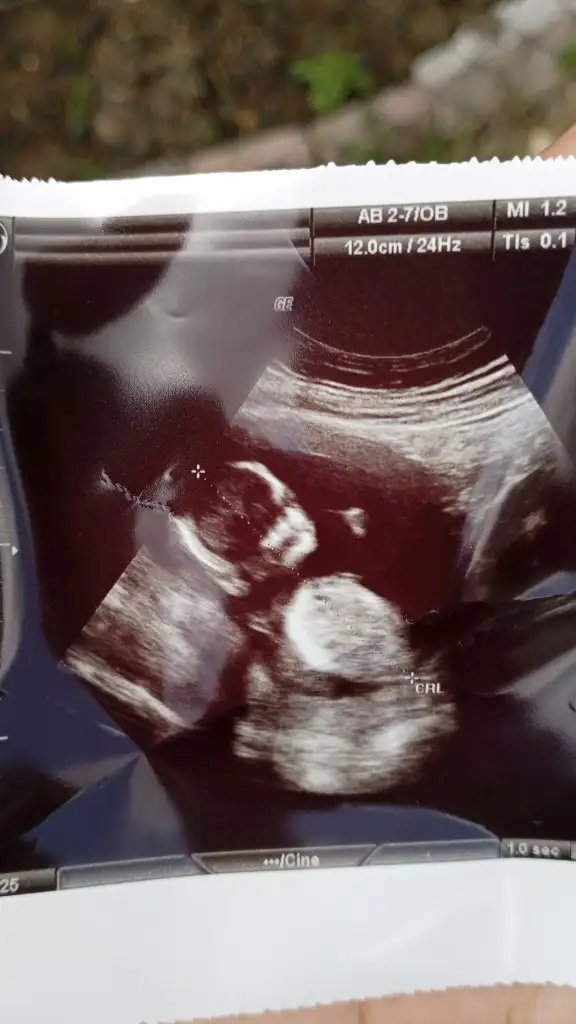

Ayy banada bakın 😀 10+3 karından ultrason

Bana da bakar mısınız 9+3